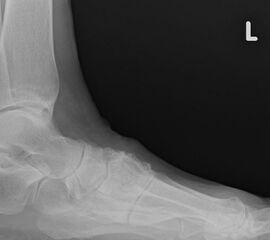

Bei nicht traumatischen Arthrosen am Tarsometatarsale (TMT) II und III Gelenk handelt es sich meist um proximale Überlastungsschäden bei ausgeprägtem Spreizfuß mit Instabilität im TMT I Gelenk oder auch alleiniger Hypermobilität im TMT I und dadurch fehlender Lastaufnahme über den ersten Strahl.

Häufig werden die Arthrosen der Lisfranc-Gelenklinie relativ spät diagnostiziert. Die Gründe dafür liegen oft daran, dass die Patienten selbst einen Schmerz an der Fußwurzel nicht mit dem Symptomkomplex Spreizfuß und Hallux valgus in Verbindung bringen. Auch werden in der Primärdiagnostik häufig nur vom Vorfuß Röntgenbilder angefertigt oder die angewandte Röntgentechnik erlaubt keine Einsicht in die Lisfranc-Gelenklinie.

Der ausgeprägte Spreizfuß führt bei vielen Patienten zu einer verringerten Lastübernahme am ersten Strahl. Ursache sind das medialisierte Os metatarsale I, sowie eine Hypermobilität im TMT I Gelenk. Unter Belastung weicht das Metarasale I nicht nur nach medial sondern auch nach dorsal aus, was die Belastung der Ossa metatarsalia II und III erhöht. Das typische klinische Symptom ist eine Transfer­metatarsalgie. Diese kann bereits bei einer isolierten Hypermobilität im TMT I auftreten. Sobald es zu einer isolierten Elevation des ersten Strahles unter Belastung kommt, steigt die Beanspruchung der medialen Metatarsalia. Weniger häufig sind posttraumatische Arthrosen, die nach Frakturen an den Basen der Metatarsalia oder (Sub-) Luxationen in der Lisfranc-Gelenklinie entstehen.

Bei den proximalen Überlastungsschäden mit Arthroseentwicklung im Übergang zur Fußwurzel am TMT II, seltener TMT III, beklagen die Patienten Schmerzen an der Fußwurzel vor allem beim Barfuß laufen oder in leichtem Schuhwerk. Auch kommt es häufig zu einer Affektion des N. peronaeus profundus, wenn ein dorsaler Osteophyt der tarsometatarsalen Gelenke vorliegt und der Nerv durch den Druck des Schuhs gegen die Knochenkante gedrückt wird. Die Kompression des Nervens ruft Beschwerden eines vorderen Tasaltunnelsyndroms hervor mit Dysästhesien oder Schmerzen im Nervenverlauf bis in den Interdigitalraum D1/2.

Diagnostik

Eine Röntgenaufnahme unter Belastung mit Abbildungen des ganzen Fußes a. p. (mit 15-20° Röhrenkippung) und seitlich, sowie Schrägaufnahmen, reichen meist zur Diagnose. Manchmal ist ein MRT und DVT ergänzend hilfreich. Selten wird die Indikation für ein SPECT CT gestellt (Abb. 6).